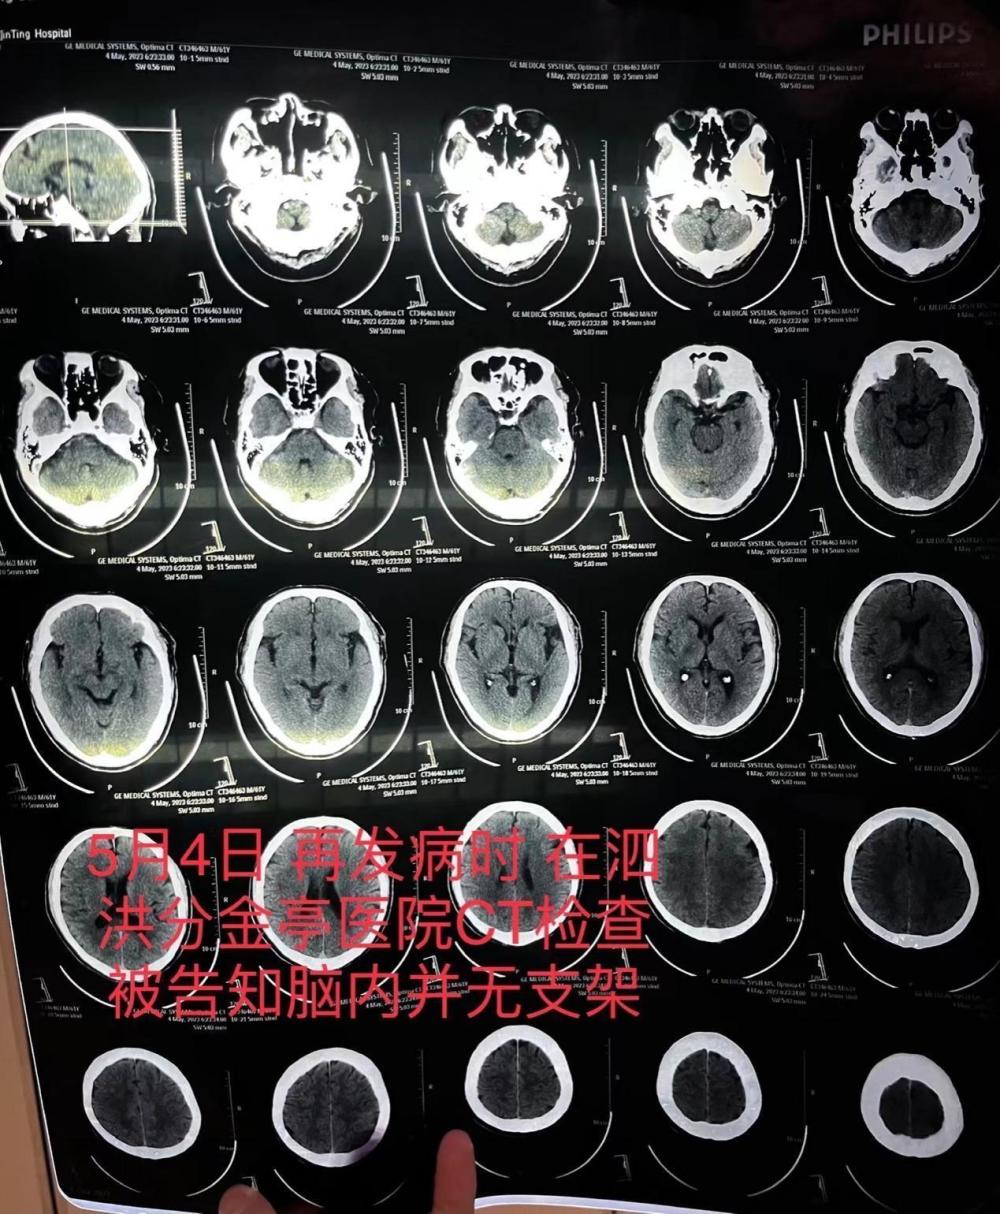

5月4日,朱老先生突发严重脑梗,被救护车送至江苏省宿迁市泗洪县分金亭医院抢救。CT检查发现,其颅内段部分动脉已严重堵闭,未发现此前植有支架。家属不相信这个检查结果,朱老先生又被转入宿迁市第一人民医院,曾作为主刀医生的齐某此时承认,之前未能在患者颅内血管成功植入支架。